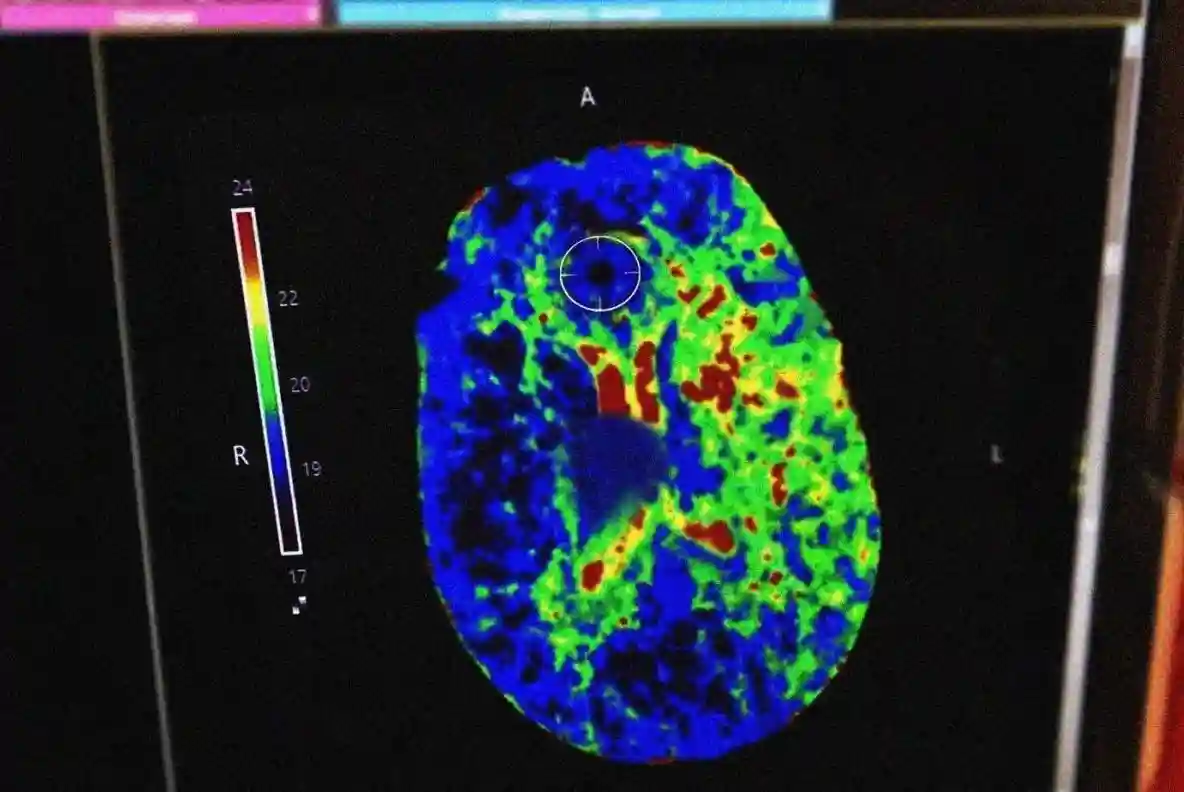

В ОКБ женщине провели полный комплекс обследований, после чего выполнили тромболизис и тромбэкстракцию — современные методы лечения инсульта.